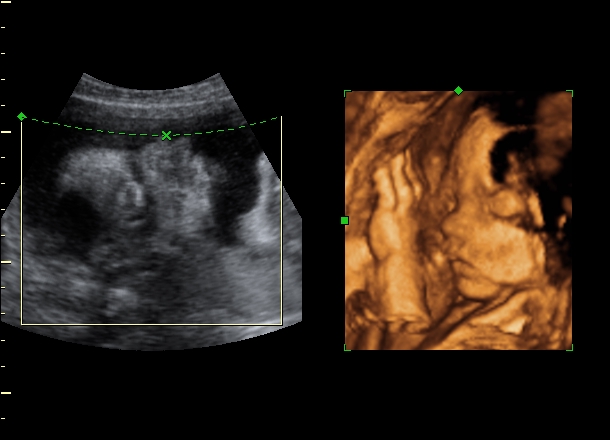

PRIKOLISTKA Опубликовано: 7 августа, 2009 Автор Жалоба Share Опубликовано: 7 августа, 2009 10- я неделя 11 - я 12- я 17-я 22- я 27-я Цитата Ссылка на комментарий Поделиться на других сайтах More sharing options...